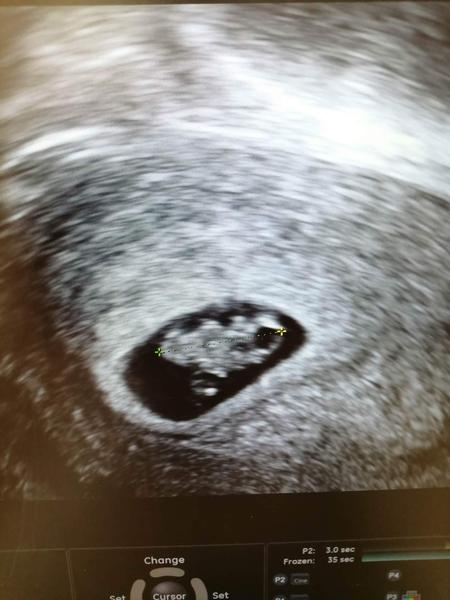

@lucipi náš Eskymáci ze včerejší kontroly, srdíčko bylo krásné vidět. No, ale pak přišla zpráva o tom, že mám špatné hodnoty štítné žlázy a musím brát léky. Tak jsem trochu naštvaná, proč mi léky nedali hned po pozitivní krvi- je to totiž hodně nebezpečné. Tak mě ve středu čeká endokrinologie